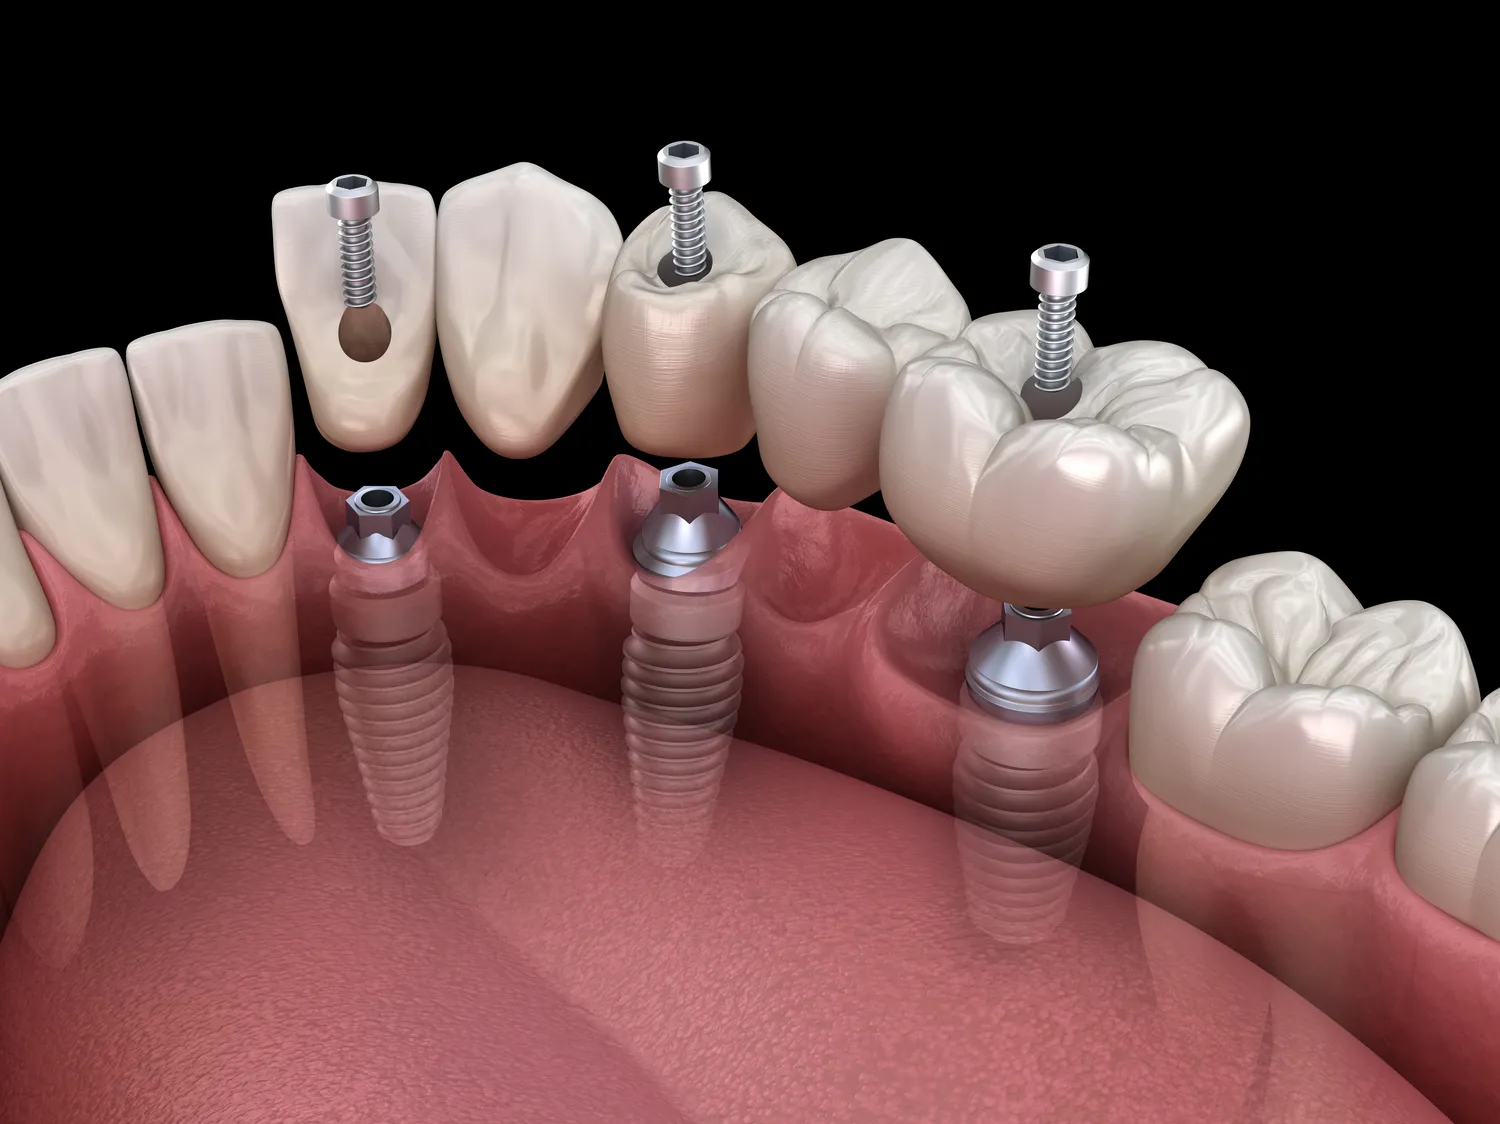

Implanty zębowe to coraz bardziej popularne rozwiązanie w stomatologii, szczególnie w przypadku utraty zębów. Koszt implantów w górnej szczęce może się znacznie różnić w zależności od kliniki, lokalizacji oraz doświadczenia lekarza. W Polsce ceny implantów wahają się od kilku do kilkunastu tysięcy złotych za jeden implant. W większych miastach, takich jak Warszawa czy Kraków, ceny mogą być wyższe ze względu na większe koszty utrzymania klinik oraz wyższą konkurencję. Warto również zwrócić uwagę na to, że niektóre kliniki oferują pakiety, które obejmują nie tylko sam implant, ale także dodatkowe usługi, takie jak konsultacje, zdjęcia rentgenowskie czy nawet protezy tymczasowe. Wybierając klinikę, warto zwrócić uwagę na opinie pacjentów oraz certyfikaty potwierdzające jakość usług. Często można znaleźć promocje lub rabaty dla nowych pacjentów, co może znacząco obniżyć całkowity koszt leczenia.

Na koszt implantów w górnej szczęce wpływa wiele czynników, które warto rozważyć przed podjęciem decyzji o leczeniu. Przede wszystkim rodzaj użytych materiałów ma kluczowe znaczenie dla ostatecznej ceny. Implanty wykonane z tytanu są najczęściej stosowane i uznawane za najbardziej trwałe, jednak ich cena może być wyższa niż innych materiałów. Dodatkowo technologia stosowana przy wszczepianiu implantów również wpływa na koszt. Nowoczesne metody, takie jak wszczepienie natychmiastowe czy cyfrowe planowanie zabiegu, mogą wiązać się z wyższymi wydatkami, ale często zapewniają lepsze efekty i krótszy czas leczenia. Kolejnym czynnikiem jest stopień skomplikowania zabiegu – jeśli pacjent wymaga dodatkowych procedur, takich jak przeszczep kości czy sinus lift, całkowity koszt może wzrosnąć. Również doświadczenie i renoma lekarza mają znaczenie; bardziej doświadczeni specjaliści mogą pobierać wyższe stawki za swoje usługi.

Decydując się na implanty w górnej szczęce, należy pamiętać o dodatkowych kosztach, które mogą pojawić się w trakcie całego procesu leczenia. Oprócz samego wszczepienia implantu pacjent często musi liczyć się z wydatkami na diagnostykę, takie jak zdjęcia rentgenowskie czy tomografia komputerowa, które są niezbędne do prawidłowego zaplanowania zabiegu. Po wszczepieniu implantu konieczne mogą być wizyty kontrolne oraz ewentualne zabiegi korekcyjne, co również generuje dodatkowe koszty. Warto również uwzględnić wydatki na leki przeciwbólowe oraz antybiotyki przepisane przez lekarza po zabiegu. Niektóre kliniki oferują pakiety obejmujące wszystkie te usługi w atrakcyjnej cenie, co może być korzystnym rozwiązaniem dla pacjentów. Dodatkowo warto pomyśleć o przyszłych kosztach związanych z protetyką – po zakończeniu procesu gojenia konieczne będzie wykonanie korony protetycznej na implancie, co również wiąże się z dodatkowymi wydatkami.

Proces gojenia po wszczepieniu implantów w górnej szczęce jest kluczowym etapem, który wpływa na ostateczny sukces leczenia. Czas gojenia może różnić się w zależności od indywidualnych predyspozycji pacjenta oraz skomplikowania zabiegu. Zazwyczaj proces ten trwa od kilku tygodni do kilku miesięcy. Po pierwszym etapie wszczepienia implantu następuje okres osteointegracji, czyli zrośnięcia implantu z kością. W tym czasie ważne jest unikanie nadmiernego obciążania implantu oraz przestrzeganie zaleceń lekarza dotyczących diety i higieny jamy ustnej. W przypadku pacjentów, którzy przeszli dodatkowe zabiegi, takie jak przeszczepy kości, czas gojenia może być dłuższy. Po zakończeniu procesu gojenia konieczne jest wykonanie korony protetycznej na implancie, co również wymaga czasu na odpowiednie przygotowanie i dopasowanie. Warto pamiętać, że każdy organizm reaguje inaczej na zabieg i czas gojenia może się różnić w zależności od wielu czynników, takich jak wiek pacjenta, stan zdrowia czy nawyki żywieniowe.

Implanty w górnej szczęce oferują wiele korzyści dla pacjentów borykających się z utratą zębów. Przede wszystkim zapewniają one stabilność i funkcjonalność porównywalną z naturalnymi zębami, co pozwala na komfortowe jedzenie i mówienie. Dzięki zastosowaniu implantów można uniknąć problemów związanych z noszeniem protez ruchomych, które często są mniej wygodne i mogą powodować dyskomfort. Kolejną zaletą implantów jest ich estetyka – dobrze wykonane implanty wyglądają naturalnie i poprawiają ogólny wygląd uśmiechu pacjenta. Ponadto implanty wspierają strukturę kostną szczęki, zapobiegając jej zanikanie w miejscach utraty zębów. To ważne dla zachowania zdrowia jamy ustnej oraz dla uniknięcia dalszych problemów stomatologicznych w przyszłości. Implanty są również bardzo trwałe; przy odpowiedniej higienie i regularnych wizytach kontrolnych mogą służyć przez wiele lat, a nawet przez całe życie pacjenta.

Cały proces leczenia implantologicznego obejmuje kilka etapów i może trwać od kilku miesięcy do nawet roku, w zależności od indywidualnych potrzeb pacjenta oraz skomplikowania przypadku. Pierwszym krokiem jest konsultacja ze specjalistą oraz wykonanie niezbędnych badań diagnostycznych, co zazwyczaj zajmuje kilka dni lub tygodni. Następnie następuje etap wszczepienia implantu – ten zabieg trwa zazwyczaj od 1 do 2 godzin i odbywa się w znieczuleniu miejscowym lub ogólnym, w zależności od preferencji pacjenta oraz wskazań medycznych. Po wszczepieniu implantu rozpoczyna się proces gojenia oraz osteointegracji, który trwa średnio od 3 do 6 miesięcy; w tym czasie implant zrasta się z kością szczęki i staje się stabilny. Po zakończeniu tego etapu konieczne jest wykonanie korony protetycznej na implancie, co również wymaga czasu na odpowiednie przygotowanie i dopasowanie estetyczne oraz funkcjonalne.